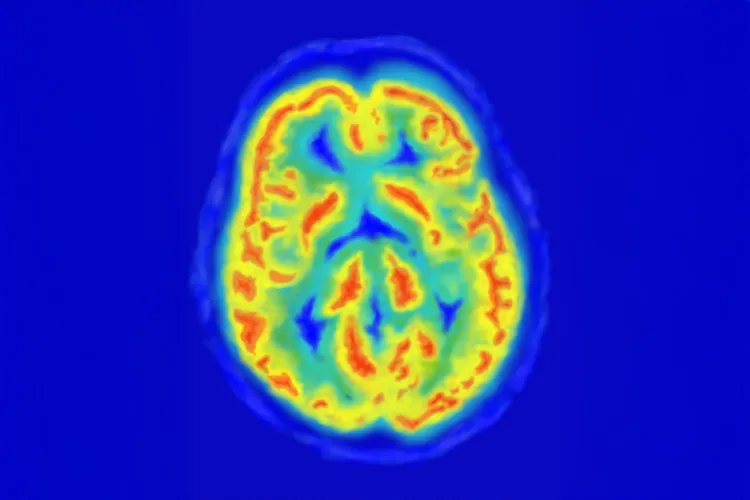

Un ejemplo de estas creaciones es su casco de mediciones que permite leer en tiempo real las señales cerebrales de un individuo en un ambiente determinado.

El dispositivo funciona con sensores metálicos que están conectados a una computadora y permiten a los investigadores realizar un electroencefalograma (EEG), una examinación que mide la actividad eléctrica del cerebro.

Un ejemplo fue un proyecto con estudiantes que estaban aprendiendo a ser emprendedores. Lo que hicieron fue colocar un dispositivo más sencillo de EEG para medir la actividad cerebral durante un pitch.